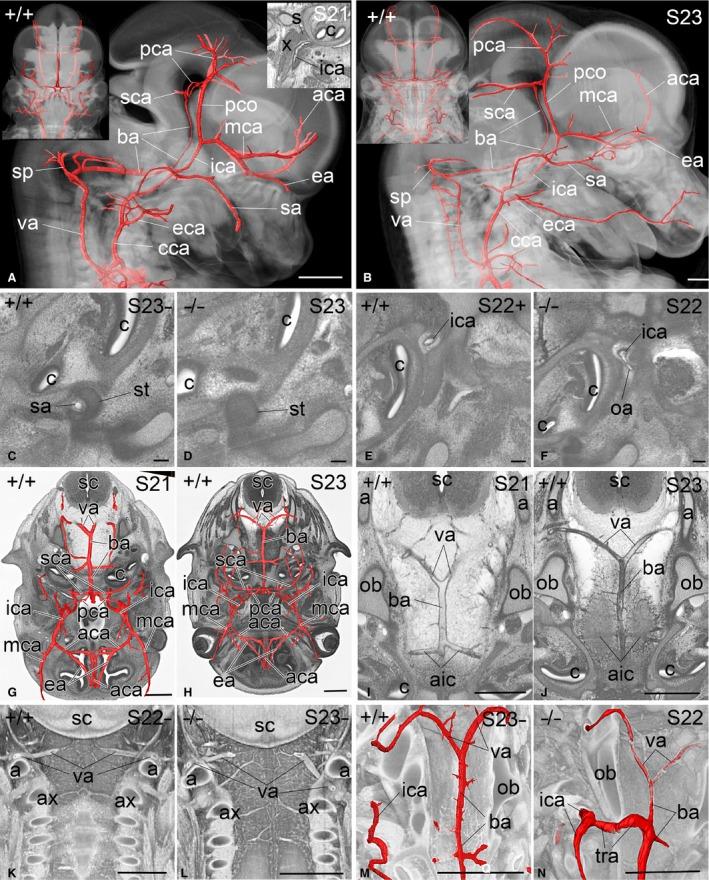

S21 - S23阶段基因正常和突变小鼠胚胎心脏及动脉的形态学、拓扑结构和尺寸

Morphology, topology and dimensions of the heart and arteries of genetically normal and mutant mouse embryos at stages S21-S23.

Accurate identification of abnormalities in the mouse embryo depends not only on comparisons with appropriate, developmental stage-matched controls, but also on an appreciation of the range of anatomical variation that can be expected during normal development. Here we present a morphological, topological and metric analysis of the heart and arteries of mouse embryos harvested on embryonic day (E)14.5, based on digital volume data of whole embryos analysed by high-resolution episcopic microscopy (HREM). By comparing data from 206 genetically normal embryos, we have analysed the range and frequency of normal anatomical variations in the heart and major arteries across Theiler stages S21-S23. Using this, we have identified abnormalities in these structures among 298 embryos from mutant mouse lines carrying embryonic lethal gene mutations produced for the Deciphering the Mechanisms of Developmental Disorders (DMDD) programme. We present examples of both commonly occurring abnormal phenotypes and novel pathologies that most likely alter haemodynamics in these genetically altered mouse embryos. Our findings offer a reference baseline for identifying accurately abnormalities of the heart and arteries in embryos that have largely completed organogenesis.

摘要

准确识别小鼠胚胎中的异常不仅取决于与发育阶段匹配的适当对照进行比较,还取决于对正常发育过程中预期的解剖变异范围的认识。在此,我们基于通过高分辨率表面显微镜(HREM)分析的全胚胎数字体积数据,对胚胎第14.5天(E14.5)收获的小鼠胚胎的心脏和动脉进行了形态学、拓扑学和度量分析。通过比较来自206个基因正常胚胎的数据,我们分析了Theiler阶段S21 - S23中心脏和主要动脉正常解剖变异的范围和频率。利用这些数据,我们在为“解读发育障碍机制(DMDD)”项目产生的携带胚胎致死基因突变的突变小鼠品系的298个胚胎中,识别出了这些结构的异常。我们展示了常见异常表型和可能改变这些基因改变的小鼠胚胎血流动力学的新病理情况的实例。我们的研究结果为准确识别已基本完成器官发生的胚胎中心脏和动脉的异常提供了参考基线。